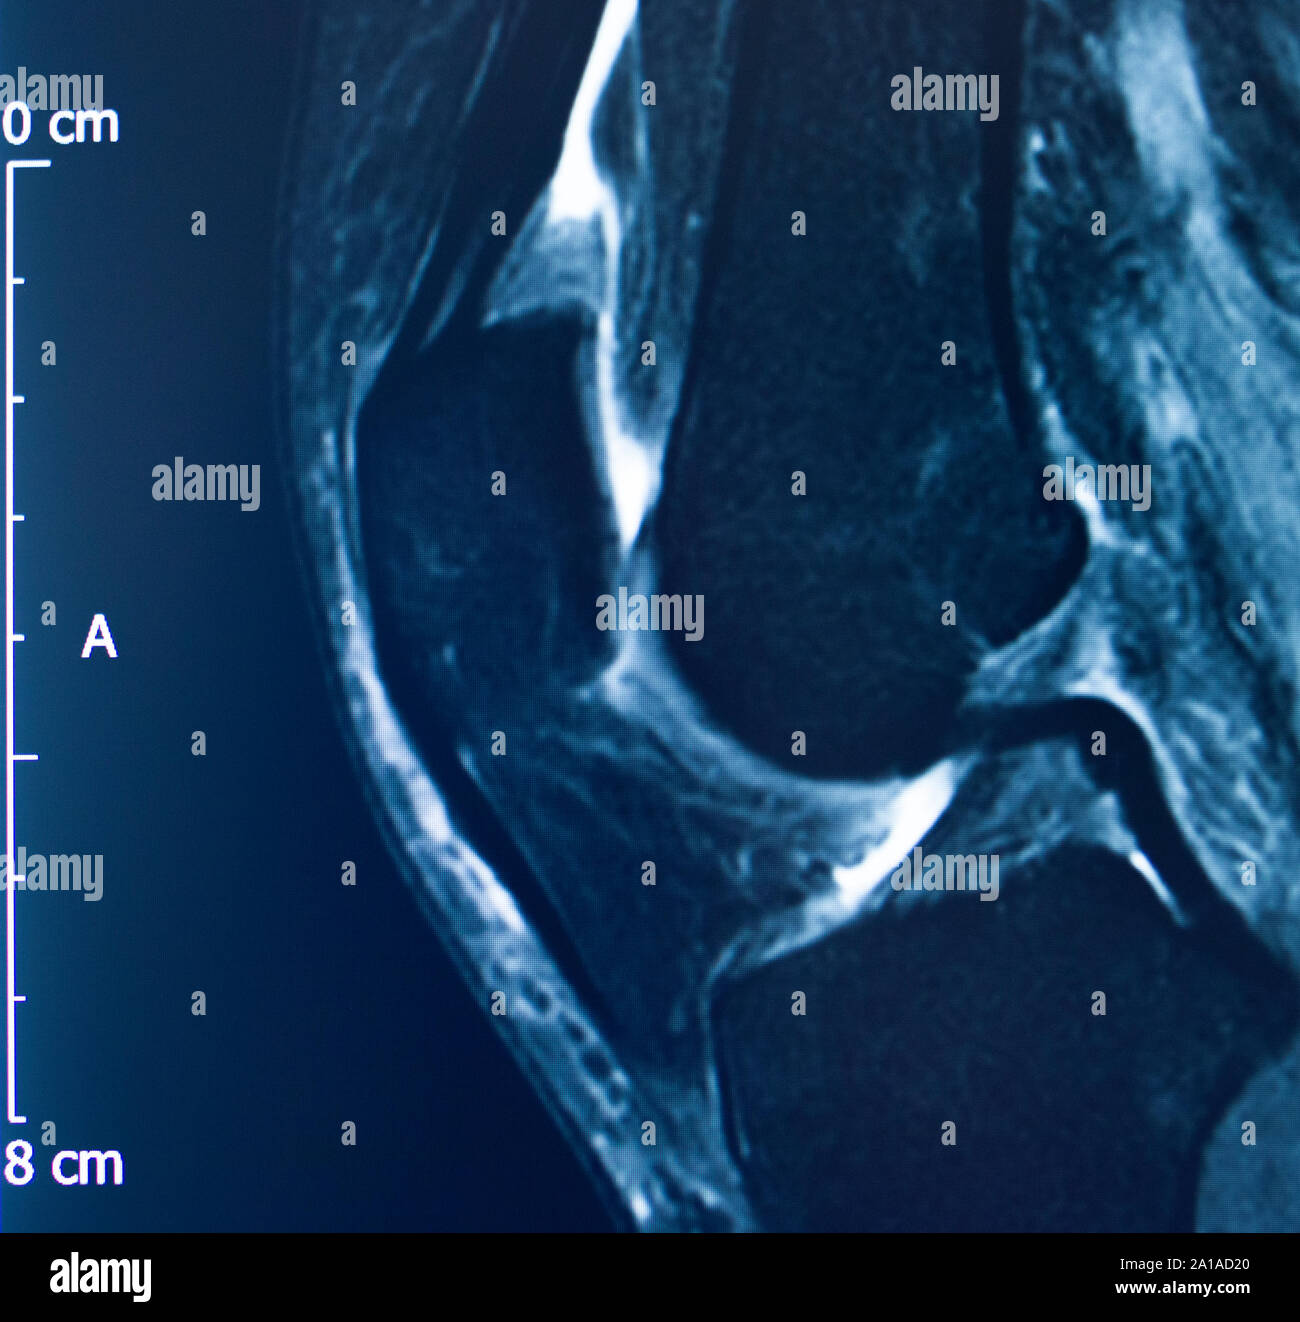

MR RIGHT KNEE Greater Waterbury Imaging Center

Knee sports injury mri mcl grade 2 tear resonance imaging orthopedic traumatology scan Best Imaging For Knee Pain 3 min read. If you have pain, weakness, or swelling around your knee, you may need a knee mri. imaging modalities used to evaluate adults with acute knee pain and the appropriateness of particular imaging. radiographic imaging should be reserved for chronic knee pain (more than six weeks) or acute traumatic pain in patients who meet specific. Best Imaging For Knee Pain.